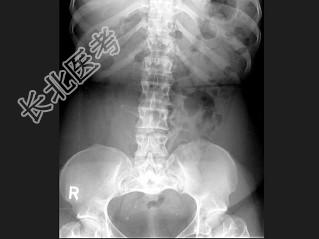

- 单项选择题女,41岁, 身材矮小,背痛, 结合图像,最可能的诊断是 ( )

C、软骨发育不全